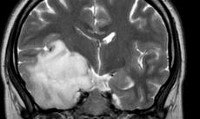

Астроцитома головного мозга. Первичная внутримозговая нейроэпителиальная (глиальная) опухоль, берущая свое начало из звездчатых клеток (астроцитов). Астроцитома головного мозга может иметь различную степень злокачественности. Ее проявления зависят от локализации и подразделяются на общие (слабость, потеря аппетита, головные боли) и очаговые (гемипарез, гемигипестезия, нарушения координации, галлюцинации, расстройства речи, изменение поведения). Астроцитома головного мозга диагностируется на основании клинических данных, результатов КТ, МРТ и гистологического исследования тканей опухоли. Лечение астроцитомы головного мозга обычно представляет собой комбинацию нескольких методов: хирургического или радиохирургического, лучевого и химиотерапевтического.

Клиническое обследование пациентов проводится неврологом, нейрохирургом, офтальмологом и отоларингологом. Оно включает неврологический осмотр, офтальмологическое обследование (определение остроты зрения, исследование полей зрения, офтальмоскопия), пороговую аудиометрию, исследование вестибулярного аппарата и психического статуса. Первичное инструментальное обследование пациентов с астроцитомой головного мозга может выявить повышенное внутричерепное давление по данным Эхо-ЭГ и наличие пароксизмальной активности по данным электроэнцефалографии. Выявление очаговой симптоматики в ходе неврологического обследования является показанием к проведению КТ и МРТ головного мозга.

Астроцитома головного мозга может быть обнаружена и при ангиографии. Установить точный диагноз и определить степень злокачественности опухоли позволяет гистологическое исследование. Получение гистологического материала возможно в ходе стереотаксической биопсии или интраоперационно (для решения вопроса об объеме хирургического вмешательства).